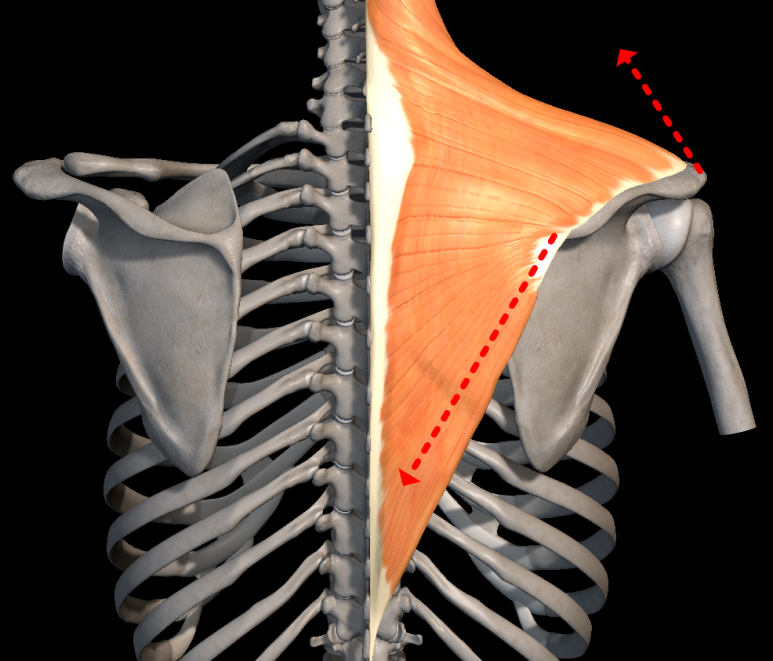

가장 흔한 이유로서 견갑골의 안정화를 도와주는 근육들의 문제가 있을 때 발생됩니다. 이러한 역할을 도와주는 근육들은 상부승모근, 전거근, 하부승모근, 능형근, 견갑거근, 소흉근이 작용해줍니다.

이중에서 전거근과, 하부 승모근은 견갑근에 내측끝에 위치해서 상방회전하면서 팔의 외전동작에서 중요한 역할을 합니다.

전거근과 승모근은 견갑골의 안정화에 매우 중요한 근육입니다. 특히 이 근육들은 상지 운동을 할 때 함께 작용하고, 특히 머리쪽으로 손을 올리는 동작들(Overhead position)에서 중요하게 작용합니다.[47][48] [49]

또한 운동이상증을 일으키는 주요 근육이기 때문에 [16] 재활 시 중요합니다.

안정적인 표면에서의 푸쉬업은 전거근(=앞톱니근)의 근력을 증가시키고, Red Cord sling으로 전반적인 근력을 향상시켜줄 수 있습니다. 불안정한 표면에서 푸쉬업을 하면 승모근 활성화가 증가하는 반면 전거근 활성화는 감소합니다.